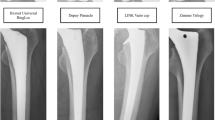

We performed THA in the supine position with a G7 OsseoTi cup (Zimmer Biomet, Warsaw, IN) as the trial cup and a femoral rasp for the Wagner cone hip stem (Zimmer Biomet) using an anterolateral approach. We made a skin incision at the anterior border of the gluteus medius muscle and accessed the hip joint through the interval between the tensor fascia lata and gluteus medius. We used a CT-based navigation system (Stryker, Freiburg, Germany) for preoperative planning, implantation, and monitoring of the hip position during examination. We resected the femoral neck based on the position indicated by the navigation system. The acetabulum was then under-reamed by 1 mm and the trial cup was inserted using the press-fit technique. The target cup placement angle was 40° of anatomical inclination. The cup anteversion was adjusted according to the required ACPL. Finally, femoral rasping was performed. The final rasp was used for the examination. Femoral anteversion was matched to the native femoral anteversion using the navigation system. When stem anteversion was changed, it was increased or decreased by 20° with respect to the native femoral anteversion. We used a trial head of 32 mm in diameter, and the neck size was selected so that the postoperative leg-length discrepancy and global offset compared with the contralateral side were almost same in each case according to the navigation system. After THA, a seat-type pressure sensor (I-SCAN, Nitta, Osaka, Japan) for real-time monitoring was placed between the iliopsoas muscle and anterior pelvic wall or anterior cup edge using an ilioinguinal approach (Fig. 1A,B). We used one sensor seat per sample. The sensor seat for each specimen was calibrated in advance under the same conditions.

Photographs of the seat-type pressure sensor for real-time monitoring of the surface pressure of the iliopsoas muscle (I-SCAN, Nitta, Osaka, Japan). (A) The sensor is 0.1 mm thick with dimensions of 10 × 10 mm. (B) The pressure sensor was placed between the iliopsoas muscle and anterior cup edge via an ilioinguinal approach. (C) Photograph showing the condition of the anterior cup protrusion length. (D–F) A typical case of the maximum surface pressure of the iliopsoas muscle with the hip in 20° of extension. Anterior cup protrusion length: (D) 0 mm, (E) 3 mm, (F) 6 mm.